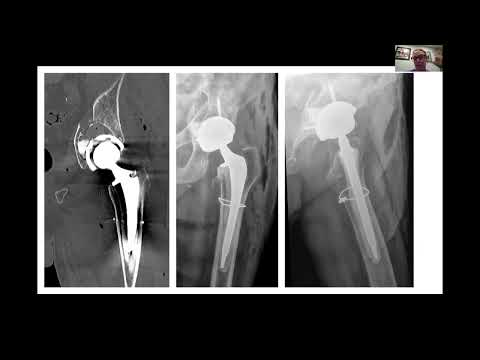

IlluminOss allows you to put screws where you want them, giving you stability, strength, and flexibility in your difficult cases. 🦴 #IlluminOss #Spreadthelight #Orthopedics

Pelvis is an approved indication in the US. For more detailed procedural information including Indications, Warnings, Cautions, Risks & Contraindications, visit illuminoss.com.